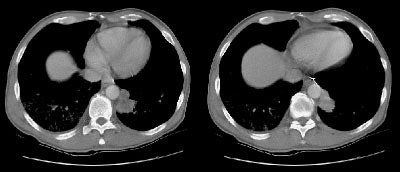

Example 1: This patient with non-small-cell lung cancer had a large necrotic primary tumor (T) and a large left adrenal metastasis (white arrows).

Example 2: In this patient with a T1N0 adenocarcinoma of the right lung, the staging CT scan revealed a heterogeneously enhancing mass in the left lobe of the liver (white arrows) and a low density mass in the left adrenal (yellow arrows). The liver lesion was subsequently shown to be an hemangioma and the adrenal lesion an adenoma. CT commonly detects other lesions which do not represent metastases, but which require further evaluation.